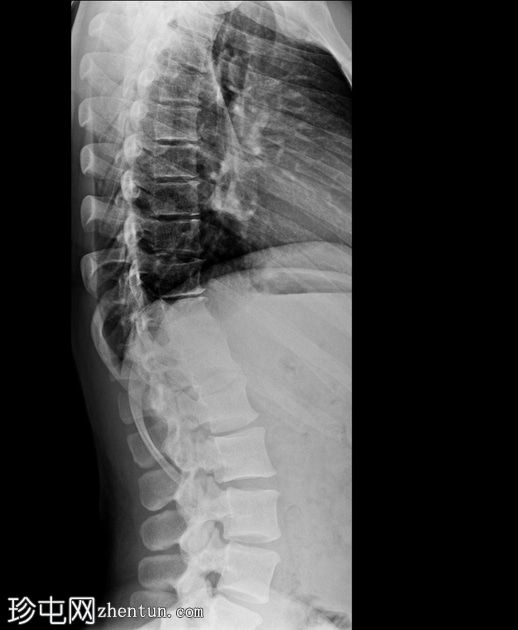

侧位片

胸腰段交界处可见先天性脊柱侧弯,右侧凸出明显。

胸腰段交界处可见右侧完全节段性半椎体。

腰椎严重旋转。